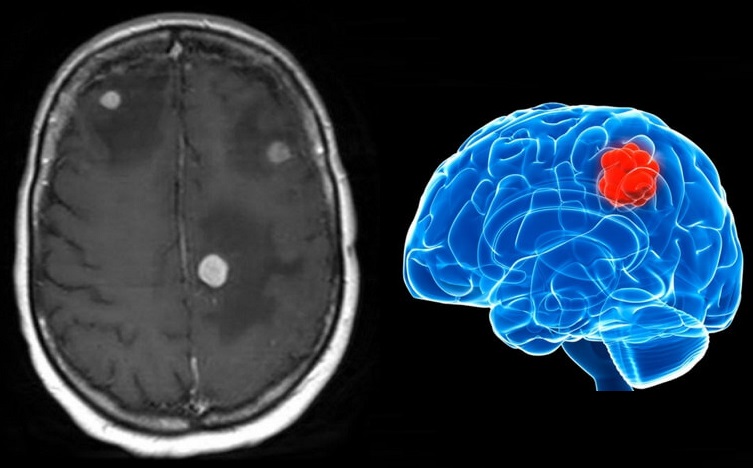

【视频】脑转移瘤治疗概述,脑转移应该选哪种方案进行治疗?

肺癌是全世界肿瘤中发病率和死亡率最高的恶性肿瘤,其中肺癌的脑转移会严重影响肺癌患者的预后及生存期,导致死亡率高于非脑转移患者。 在肺癌中最常见的病理类型是非小细胞肺癌(Non-sm…